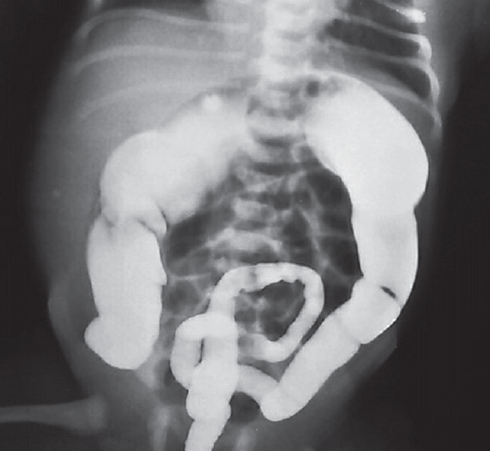

Рис. 2. Вид живота перед операцией

Fig. 2. Abdomen view before the surgery

После выполнения высокого промывания толстой кишки отошло большое количество кашицеобразного стула и газов, живот уменьшился в размерах. Диагноз кишечной непроходимости был исключен. В последующие дни ребенок не срыгивал, питание усваивал, регулярно отходил самостоятельный стул. Выписан на амбулаторное лечение с диагнозом: гипоксически-ишемическое поражение ценральной нервной системы, вегето-висцеральный синдром. На 2-м месяце жизни появилась тенденция к задержке стула, которая нарастала в динамике. Ребенок наблюдался педиатром и ни разу не был осмотрен хирургом. В хирургический стационар поступил в возрасте 10 мес. с клиникой кишечной непроходимости (рис. 2).